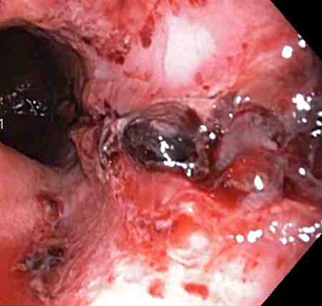

Mallory-Weiss tear

Mallory Weiss tear after application of through-the-scope clip results in haemostasis

From the personal collection of Douglas Adler; used with permission